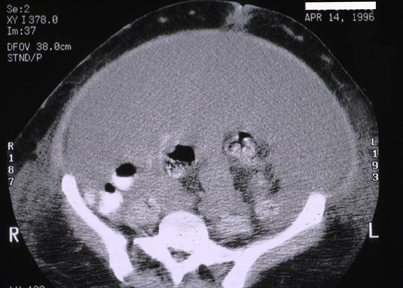

| These abdominal CT scans above and below reveal hepatic infarction with decreased attenuation (darker) caused by hepatic vein thrombosis with Budd-Chiari syndrome in a patient with anti-phospholipid syndrome. In the view above there is marked ascites. In the view below there is splenomegaly as well as more prominent subcutaneous veins (caput medusa) filled with bright contrast. In the view at the bottom of the page, below the level of the liver, there is abdominal enlargement from massive ascites. |